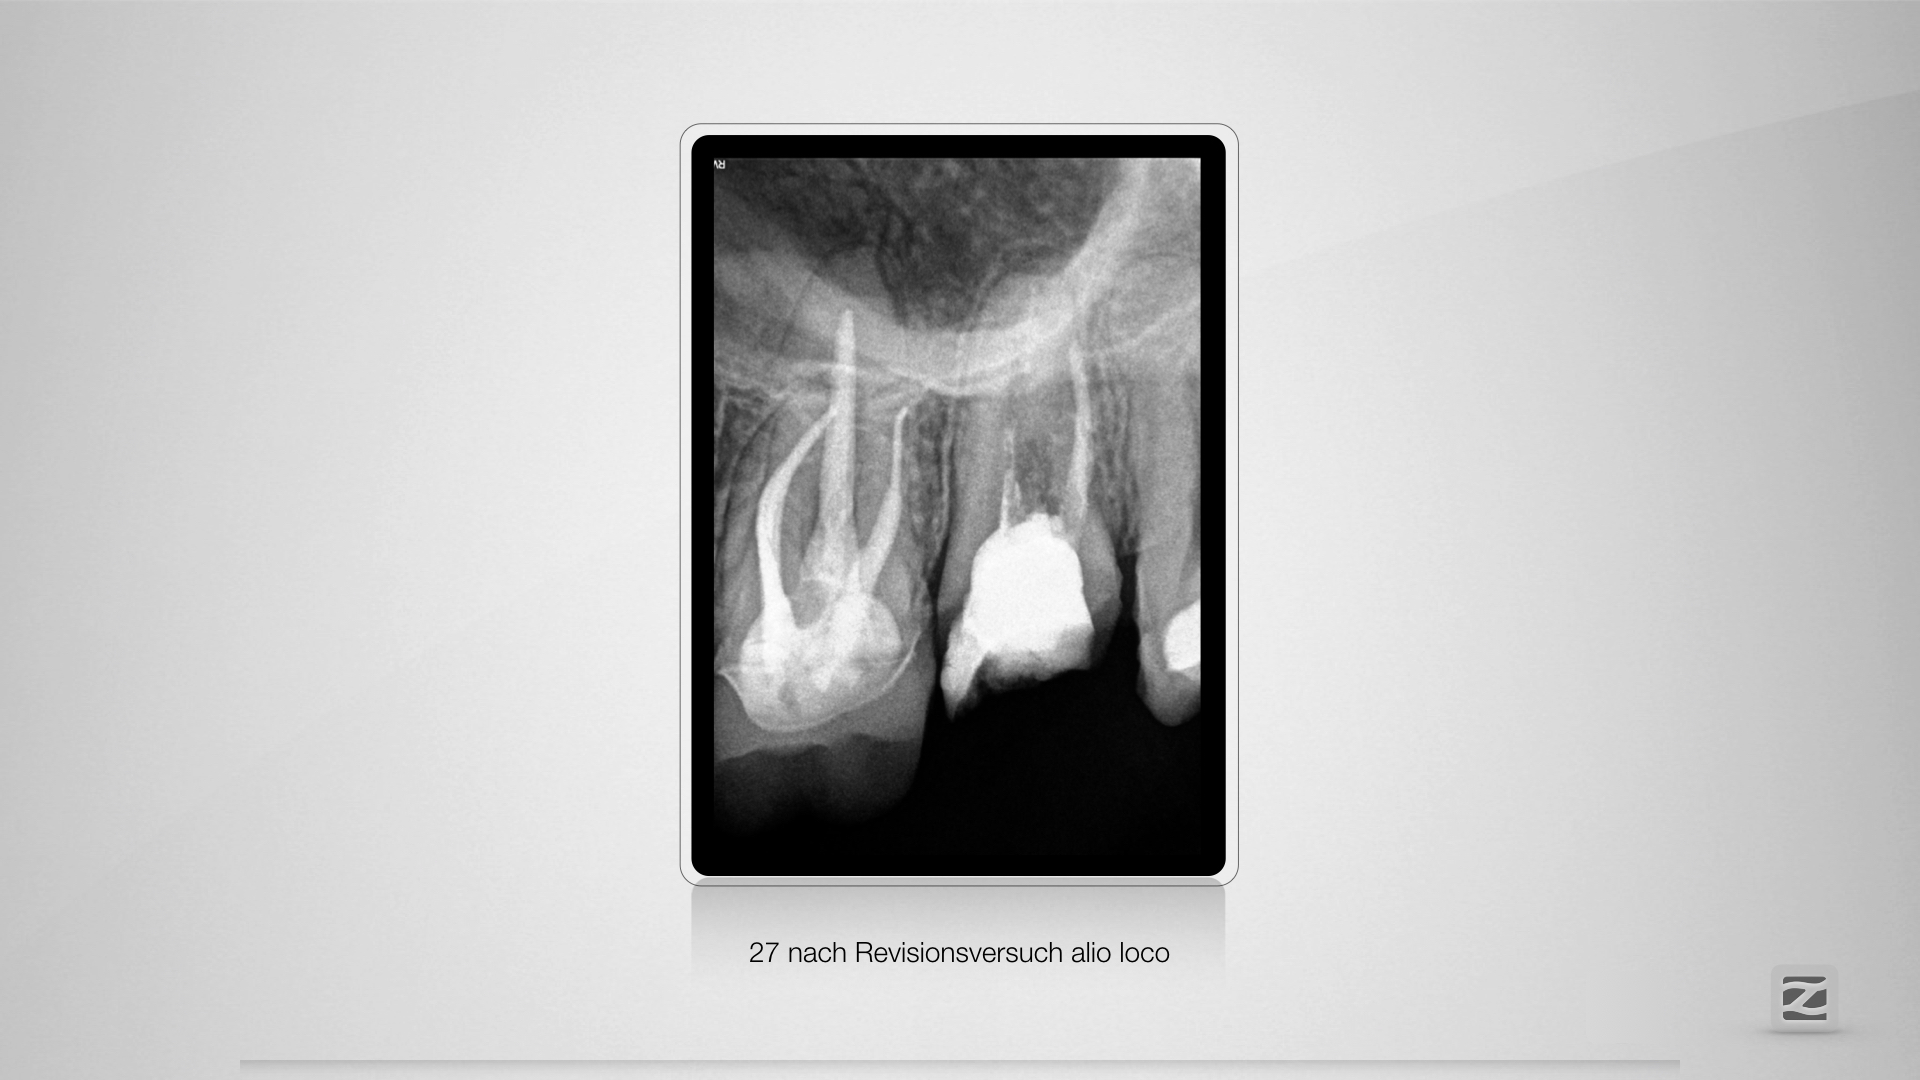

Fast getroffen ist auch vorbei!